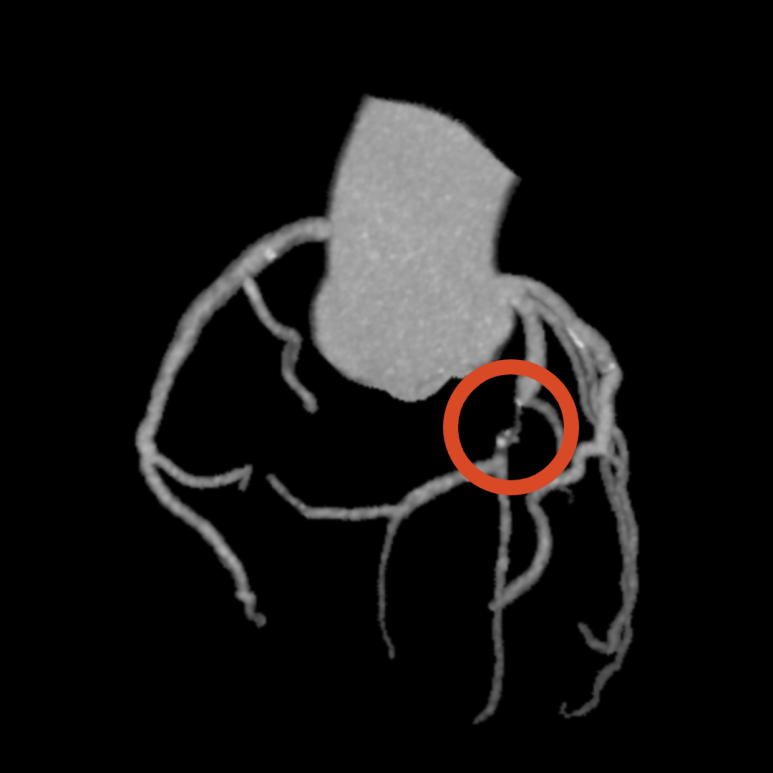

ECG·심초음파 특이 소견 없음. 관상동맥 CT 검사 결과 좌관상동맥 2부위 중증 협착 명확히 확인되었고, 즉시 스텐트 치료 필요성 높아 상급병원으로 전원.

• 3D 관상동맥: 협착 부위 3D 관상동맥: 협착 부위

• 좌측 관상동맥 2곳에서 협착 발견 좌측 관상동맥 2곳에서 협착 발견